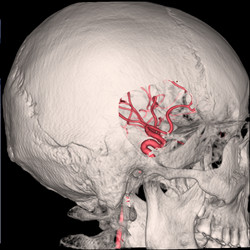

血管影像透明化技术让动脉结构一览无遗,更精准引导动脉瘤治疗。

▲前交通动脉瘤的血管造影图,红色一点被称为“定时炸弹”,

一旦破裂,死亡或病残率极高。